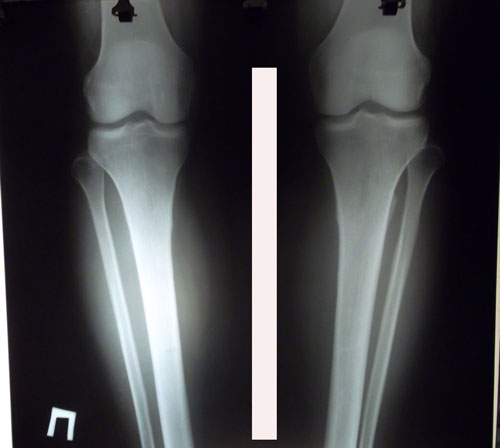

Дата операции 14.04.2016г.

Дата снятия аппаратов 01.08.2016г.

Срок лечения 106 дней.